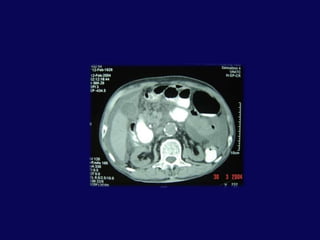

BT: pankreas orta hatta laserasyon ve peripankreatik sıvı

Peripankreatik sıvıya perkütan drenaj kateteri . İlk gün 750 cc drenajİşlem sonrası 2. gün genel durum iyi.  Dren debisi 200 ccDren debisi giderek azalan hastanın 4. günde debisi 100 cc. Dren kültürü steril.7. gün kontrole gelmek üzere taburcu

Hasta işlem sonrası 23. gününde ateş, bulantı, kusma şikayetleriyle yeniden yatırıldı.BT’ de karaciğer ve mide arasında 6x5 cm’lik bir koleksiyon tespit edildi. Perkütan drenaj uygulandı. 200 cc geleni oldu.